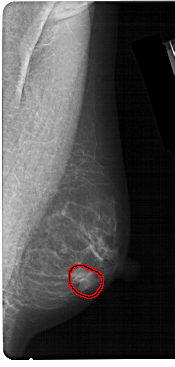

A_1304_1.RIGHT_CC

RIGHT_CC LINES 5491 PIXELS_PER_LINE 2431 BITS_PER_PIXEL 12 RESOLUTION 43.5 OVERLAY

FILE: A_1304_1.RIGHT_CC.OVERLAY

TOTAL_ABNORMALITIES 1

ABNORMALITY 1

LESION_TYPE MASS SHAPE OVAL MARGINS CIRCUMSCRIBED

ASSESSMENT 4

SUBTLETY 4

PATHOLOGY BENIGN

TOTAL_OUTLINES 1

BOUNDARY